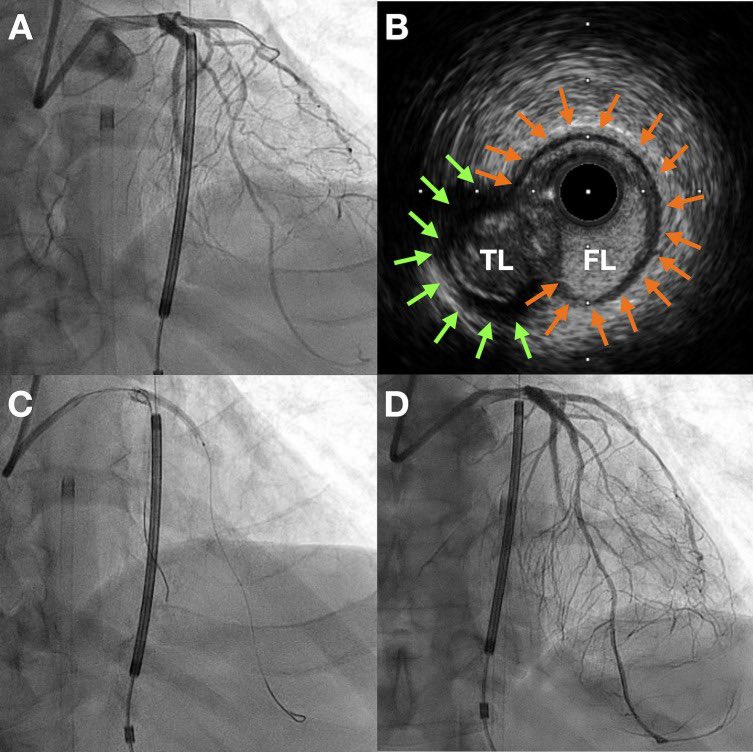

The formation of a double barrel ‘neo lumen’ HAS been described by @LAzzaliniMD et al. In fact, that is where I first learned that it is possible for the vessel wall to heal in this particular way. We have seen this in both CTOs and non-CTOs after CBA! From Lorenzo’s paper…

Here is the IVUS - one of the more notable one. It shows the various types of healing that can take place after STAR. The two that haven’t been described are formation of a lotus root and TL regression with formation of a new(!) channel.

The patient came back at 4 weeks with marked improvement in her symptoms. We scheduled her for a relook and definitive treatment with DES. This is the follow up angio! 😳 We performed IVUS and ended up treating the proximal stent by dilating it more.

A New (Kind Of) STAR Is Born! 48 year old woman with prior IWMI (@ age 36!) → Class II angina on OMT. Stress abnormal in the RCA distribution. CAG revealed RCA IS-CTO. Partner attempted #HDR unsuccessfully, and we ended up doing STAR + CB investment. What to do next?